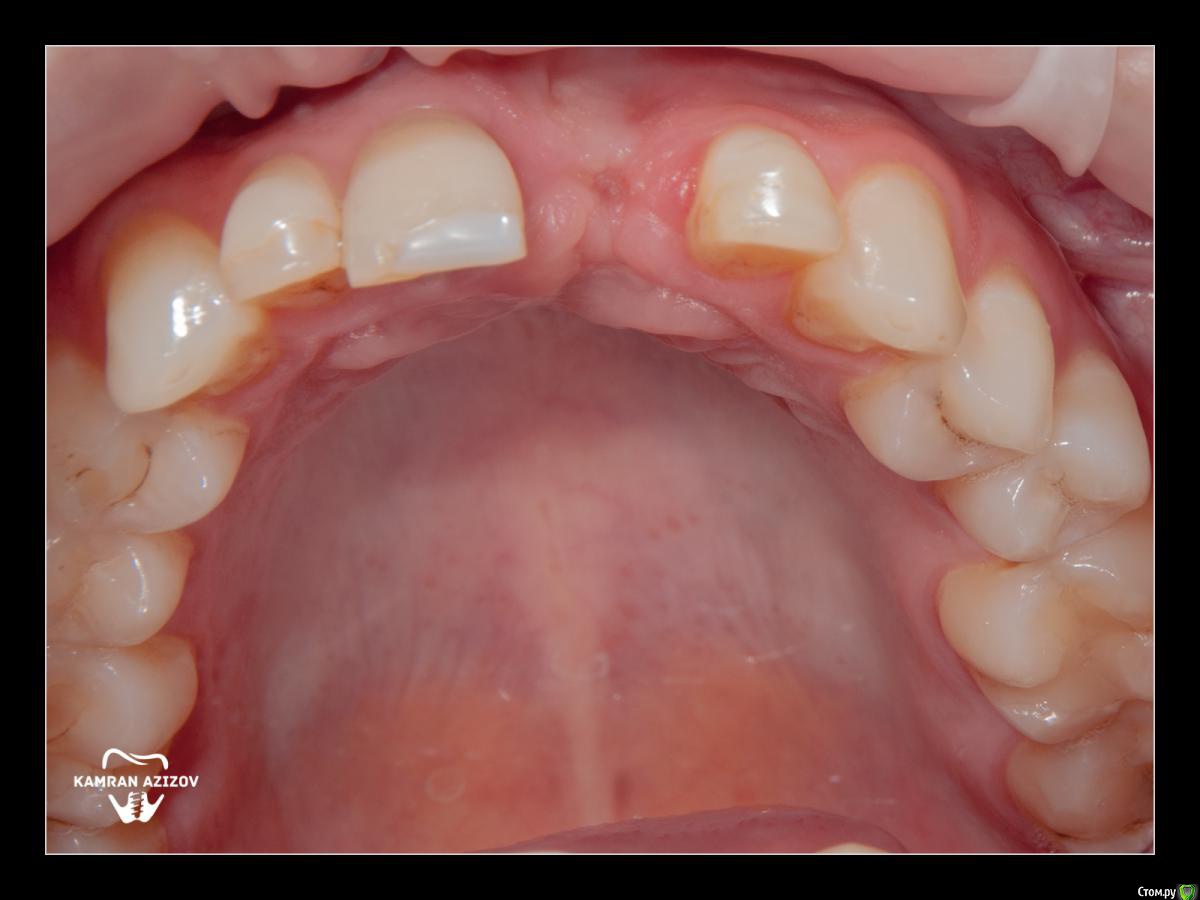

Dman Опубликовано 11 октября, 2019 Поделиться Опубликовано 11 октября, 2019 На 9 фото не понятно что, другой формирователь и корректировал десну? Ссылка на комментарий

kamranchick Опубликовано 11 октября, 2019 Автор Поделиться Опубликовано 11 октября, 2019 На 9 фото не понятно что, другой формирователь и корректировал десну?да. это такой формирователь на штраумане который винтом прикручивается, денег не было на времянку, пришлось поставить такой формик Ссылка на комментарий

Dman Опубликовано 11 октября, 2019 Поделиться Опубликовано 11 октября, 2019 да. это такой формирователь на штраумане который винтом прикручивается, денег не было на времянку, пришлось поставить такой формикс десной то что делали - выглядит как корректированная бором или лазером Ссылка на комментарий

kamranchick Опубликовано 12 октября, 2019 Автор Поделиться Опубликовано 12 октября, 2019 Не. Ничего особо не делал.Формик зарос. Немного освободил от мягких тканей. Чуть чуть скальпелечком прошёл и вкрутил Новый Ссылка на комментарий